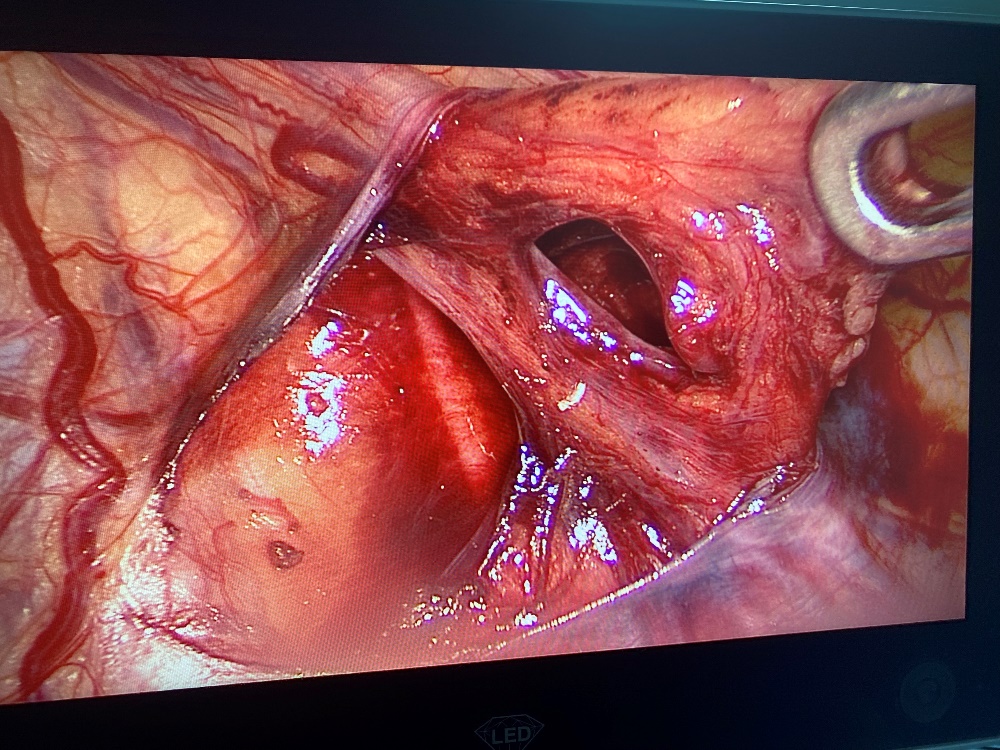

• Xác định tĩnh mạch tinh.

• Phẫu tích phúc mạc, bộc lộ động mạch, tĩnh mạch tinh kèm ống dẫn tinh.

(Bệnh nhân được phẫu thuật tại khoa Ngoại tổng hợp – BVĐK Quảng Trị)

• Tách chọn lọc tĩnh mạch tinh, thắt tĩnh mạch, bảo tồn động mạch, ống dẫn tinh.